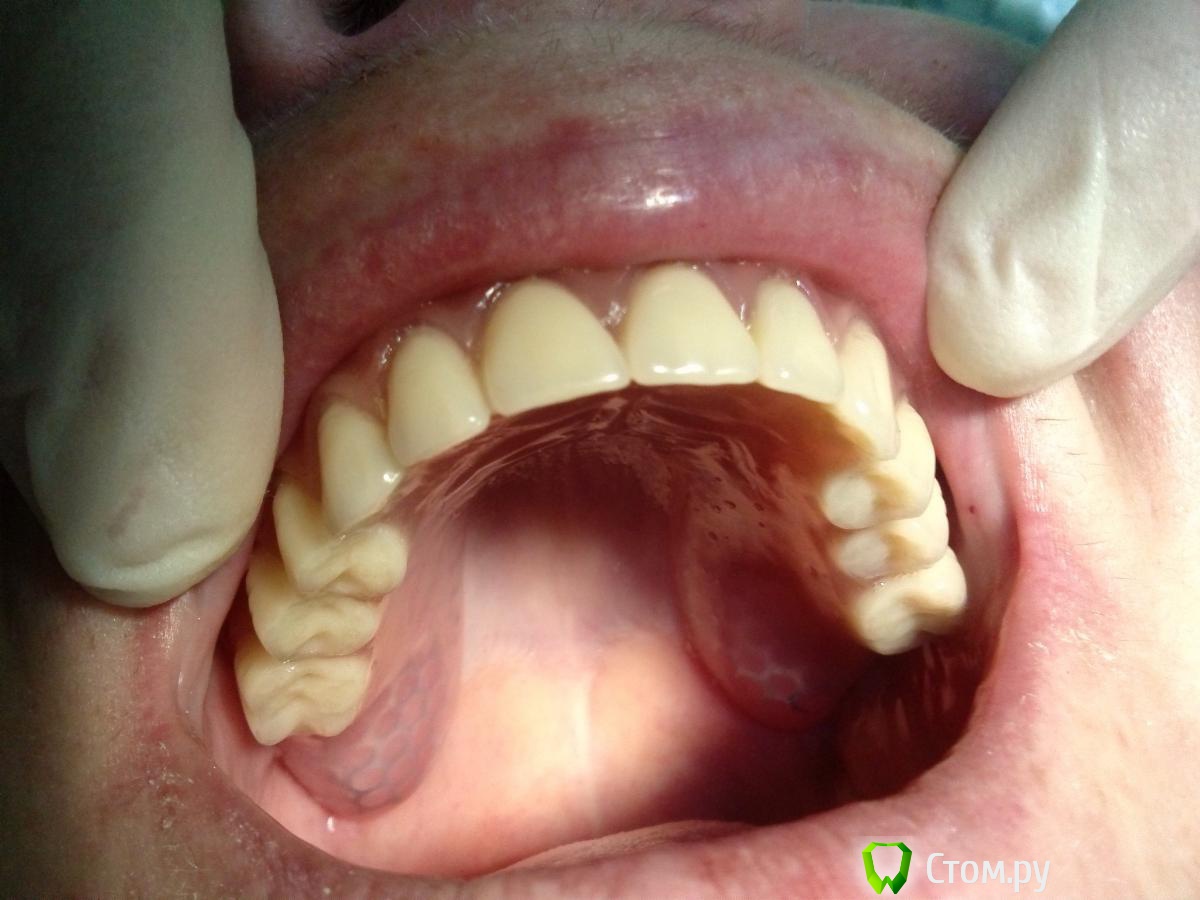

Troy Опубликовано 10 декабря, 2013 Поделиться Опубликовано 10 декабря, 2013 скорее всего плохо изолировали,придется выпиливать замки(те что в протезе),после сделайте следущее1- прокладки силикона не ставьте,а вместо них вырежте из целофана но не кольца а формы круга размером с монетку.2- приложите этот целофановый круг к абатменту и защёлкните его замком. так на все четыре3- уложите протез на протезное ложе,придерживая рукой,а другой рукой загоняйте материал в дырки которые высверлили.как заполнятся дырки, дайте больному закрыть рот в прикусе и подождите пока заполимеризуется.4- после этого протез снимется хорошо, и можете полировать.Спасибо большое. Пока думали что делать пациентка сутки носила протез. На следующий день он без проблем снялся. Вот кейс. Мои импланты и ортопедия. Один на верхней не выжил. Что скажете? Ссылка на комментарий

Sir Edward'S Опубликовано 10 декабря, 2013 Поделиться Опубликовано 10 декабря, 2013 (изменено) можно было изменить место расположение имплантов и сделать подкову смысл теряется в имплантации если все равно съёмный протез на нижней челюсти во фронтальном отделе достаточно 2 имплантов Изменено 10 декабря, 2013 пользователем Sir Edward'S 1 Ссылка на комментарий

Troy Опубликовано 10 декабря, 2013 Поделиться Опубликовано 10 декабря, 2013 можно было изменить место расположение имплантов и сделать подкову смысл теряется в имплантации если все равно съёмный протез на нижней челюсти во фронтальном отделе достаточно 2 имплантовЗачем жетогда локаторы, балки и кнопки придуманны? Ссылка на комментарий

Sir Edward'S Опубликовано 11 декабря, 2013 Поделиться Опубликовано 11 декабря, 2013 Зачем жетогда локаторы, балки и кнопки придуманны? а какой смысл пациенту при 12 имплантах носить съёмник? 1 Ссылка на комментарий